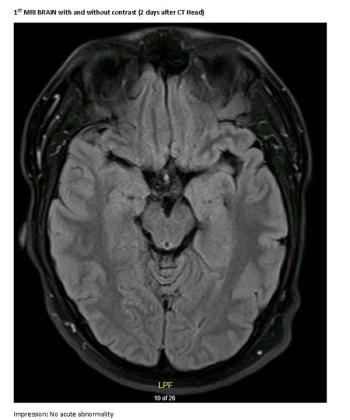

A 23-year-old male college student presents with first generalized tonic-clonic seizure followed by episodes of violent psychosis.

A generally healthy, young adult male presents with first generalized tonic-clonic seizure followed by episodes of violent psychosis.